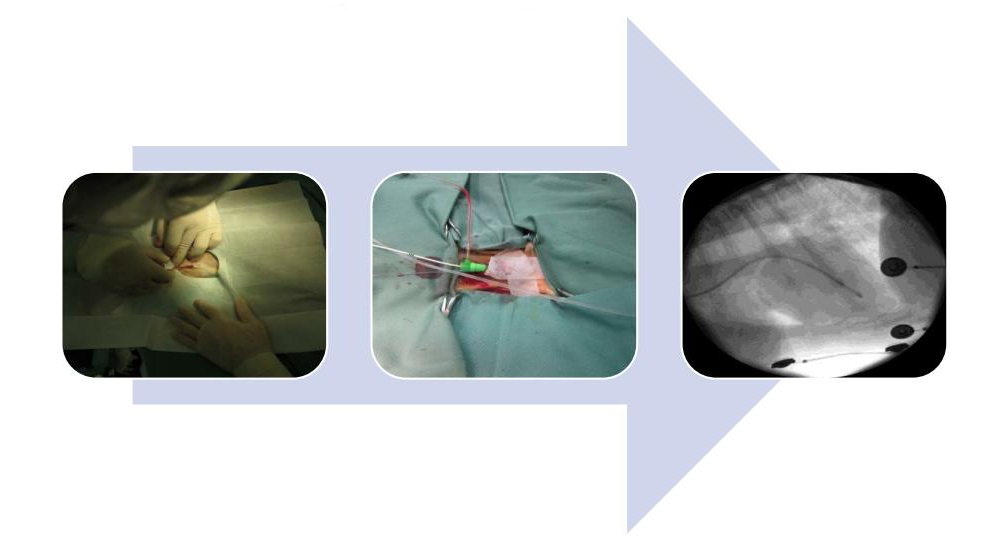

一時ペーシング留置

一時ペーシング留置は、徐脈性不整脈動物の麻酔時に利用できます。